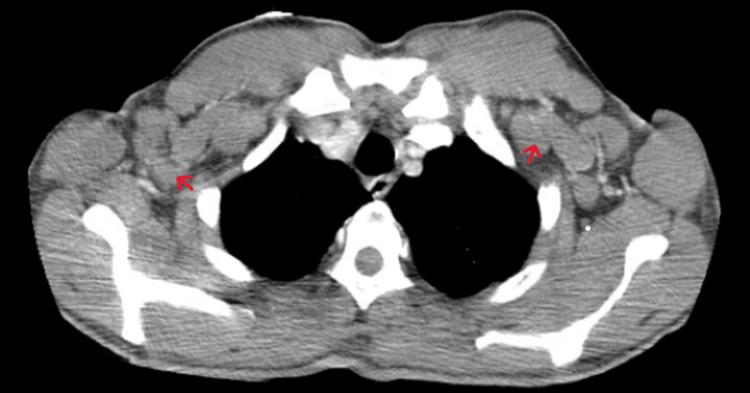

Angioimmunoblastic T-cell lymphoma (AITL) is a rare and aggressive form of peripheral T-cell lymphoma (PTCL). It can present with signs and symptoms that have broad differentials, including fevers, night sweats, and skin rashes. In this case report, we present an interesting case of a young male of Nigerian descent with recently treated malaria who presented with such symptoms and a picture that was complicated, due to an inconclusive excisional biopsy for lymphoma. He was later diagnosed with AITL. Given the patient's recent exposure to malaria, we will discuss the potential role malaria has in the development of AITL.

血管免疫母细胞性T细胞淋巴瘤(AITL)是外周T细胞淋巴瘤(PTCL)的一种罕见且侵袭性的类型。它可表现出具有广泛鉴别诊断的体征和症状,包括发热、盗汗和皮疹。在本病例报告中,我们呈现了一例有趣的病例,一名有尼日利亚血统的年轻男性,近期患疟疾并接受了治疗,他出现了上述症状,且由于淋巴瘤切除活检结果不明确,病情较为复杂。他后来被诊断为AITL。鉴于该患者近期感染过疟疾,我们将讨论疟疾在AITL发生发展中可能扮演的角色。